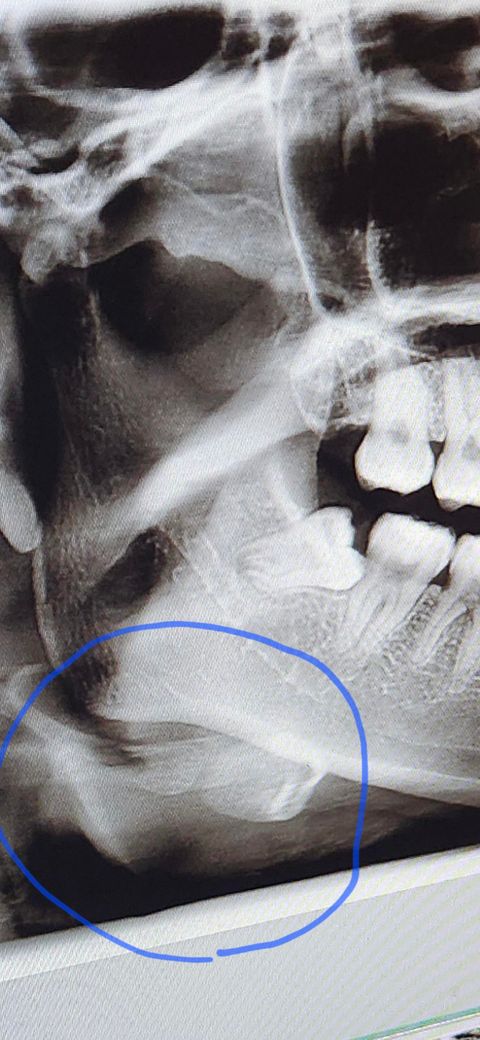

치과 엑스레이 턱에 하얀 부분 뭔가요?

치과에서 엑스레이 찍었는데요

동그라미 친 부분이 뭔지 궁금합니다

설마 치아는 아니겠죠? 왜 저렇게 치아같은 모양으로 있는건지 좀 알려주세요..

동그라미 친 부분은 치아 모양이 아니며 설골일 가능성이 높습니다.

정상 해부학적 구조(뼈)입니다 hyoid bone panoramic x ray라고 검색해보시기 바랍니다

사진으로 보이는 부분은 설골이 있는 부분으로 보입니다. 앞 꼴에 있는 것이 아니라 목에 있는 뼈가 방사선 사진상으로 보인 것으로 보입니다.